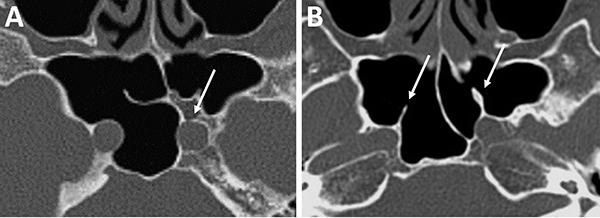

En referencia a las variantes turbinales se debe considerar la presencia de hipertrofia turbinal inferior y de cornetes medios bullosos (fig. 10). Ante la hipertrofia turbinal inferior será necesario realizar buena vasoconstricción preoperatoria asociada a luxofractura y lateralización para lograr un abordaje adecuado si es que no se asocia un tratamiento para la insuficiencia ventilatoria. Los cornetes medios bullosos representan una variante hipertrófica con neumatización de los mismos, los cuales podrán resecarse parcial o totalmente para lograr el correcto abordaje.

Figura 10: Variantes turbinales en TC cortes coronales. A) Hipertrofia turbinal inferior (asteriscos blancos); B) Cornetes medios bullosos (asteriscos blancos) y desvío septal-espolón (flecha blanca).